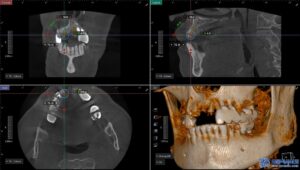

무절개 임플란트는 컴퓨터 분석을 통해

미리 계획된 경로를 따라 식립하기 때문에

절개가 필요하지 않고 출혈이 적으며

회복 속도가 빠릅니다.

특히 임플란트 성패에 중요한

식립각도에 관한 연구도

뉴스로 발표된바 있습니다.

또한, 위 사진처럼

수술가이드를 제작하여 오차 없이

정밀한 위치에 임플란트를

심을 수 있기 때문에

성공률도 높아지게 됩니다.